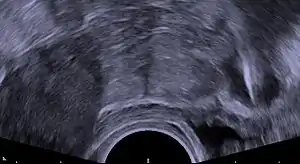

String problems: A small portion of men report that they can feel the strings during intercourse. In this case, strings can be trimmed. However, very short strings can prevent the woman from checking the strings for expulsion.[20] Medical ultrasonography may be required in such cases to check the location of the IUD.